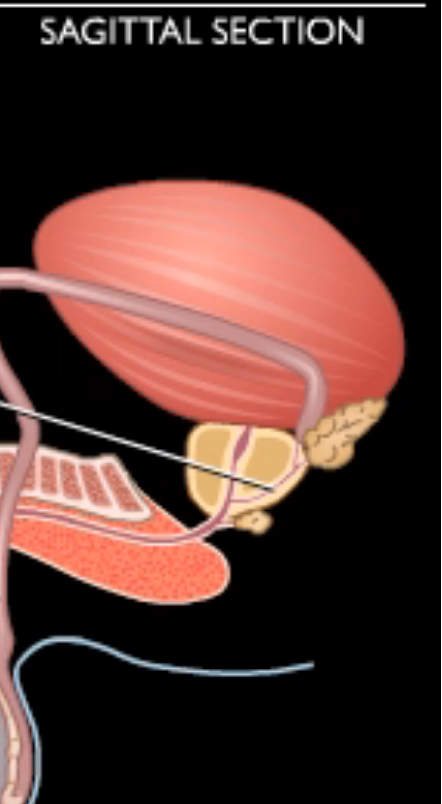

Vas deferens (ductus deferens)

Ejaculatory duct

Seminal vesicle